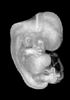

Carnegie Stage 18 (44 post-ovulatory days)

Most embryos at stage 18 are approximately 44 postovulatory days old and measure 13-17 mm in length. Distinguishing criteria for this stage include cervical and lumbar flexures, distinct notching in the hand plate, the first appearance of the elbow, eyelid folds may appear in more advanced specimens, and auricular hillocks begin to form distinct parts of the external ear.